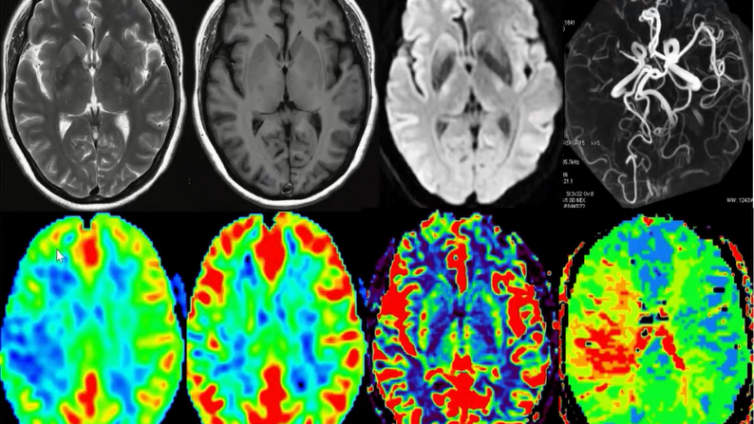

25 08月 放射科 颅脑环形强化病变的影像诊断思路总结 慢性扩展性脑内血肿慢性扩展性脑内血肿是自发性脑内血肿的一种特殊类型。脑内出血量呈少量、缓慢、持续进行,血肿不断扩大,血肿的血红蛋白分解液化,刺激周围的脑组织产生炎性反应,血肿周围胶质及纤维组织明显增生形成很厚的包膜,故又称慢性包膜性脑内血肿。影像表现> CT平扫时表现为脑实质内囊性病变,圆形,...

24 08月 放射科 脑脱髓鞘疾病(具有环形强化) 脑脱髓鞘疾病(具有环形强化)◆ 多发性硬化(MS):同心圆硬化◆ 急性播散性脑脊髓炎 (ADEM)脑脱髓鞘疾病口 病灶均分布于脑白质区口 呈多发长T1长T2信号影口 病灶呈多发环形或半环形强化,病灶大小可不一,环壁薄而均匀脑出血吸收期脑实质内出血一周后,血肿周围出现肉芽组织增生,肉芽组织内含有大量新...

23 08月 放射科 脑囊虫病理分期与影像表现 脑囊虫病理分期病理上脑实质内囊虫分四期∶口 I期∶ 囊泡期。囊虫头节含在清晰的囊液内, 囊壁薄, 周围炎症反应轻微。口 Ⅱ期∶胶样囊肿期。虫体死亡,头节开始退变,囊内液体开始变浑浊,囊泡收缩,释放的代谢物破坏血脑屏障,引起脑组织炎症反应和水肿。口 Ⅲ期颗粒结节期。囊泡皱缩,囊壁变厚,虫体及囊壁钙化,...

22 08月 放射科 颅脑环形强化病变的真菌性感染 真菌性感染脑内隐球菌感染、念珠菌感染、烟曲霉菌感染、放线菌感染均可在脑内形成脓肿。CT和MR增强扫描时呈环形强化,与脑脓肿表现相似,常难以区别。不过念珠菌性脓肿,CT增强扫描时脓肿内密度较高,常等于或低于周围脑实质,有助于与细菌性脑脓肿鉴别。烟曲霉菌性脑脓肿,环形强化之环壁常较厚且不规则。隐球菌性炎...

20 08月 放射科 脑内环形强化原发肿瘤常见于......(5) 脑内环形强化原发肿瘤常见于1. 间变性 星形细胞瘤2. 胶质母 细胞瘤3. 囊性毛细胞 星形细胞瘤4. 血管母 细胞瘤脑脓肿的并发症∶口 “子灶”形成——系脓肿壁破裂侵犯邻近组织口 脑室炎——化脓性脑室炎或室管膜炎原因较多,有时为脓肿破裂脑室所致(约50%脓肿近脑室侧的壁很薄,是脓肿破入脑室的基础)...